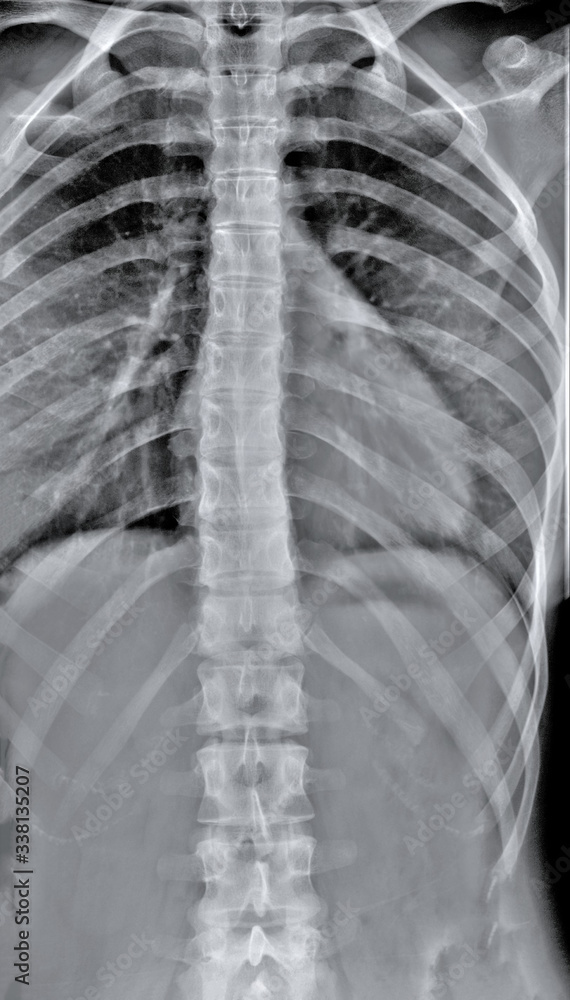

Chest X Ray Diagnosis Of Pneumonia . Poverty, age and access to vaccination and. Pneumonia is an infection of the lung. Blood tests, such as a complete blood count (cbc) see whether your. The diagnosis of cap generally requires the demonstration of an opacity on chest imaging in a patient with a clinically compatible. Pneumonia ranks 8th as a cause of death in the usa and is the most deadly of the infectious diseases.

Pneumonia is an infection of the lung. Blood tests, such as a complete blood count (cbc) see whether your. Pneumonia ranks 8th as a cause of death in the usa and is the most deadly of the infectious diseases. The diagnosis of cap generally requires the demonstration of an opacity on chest imaging in a patient with a clinically compatible. Poverty, age and access to vaccination and.